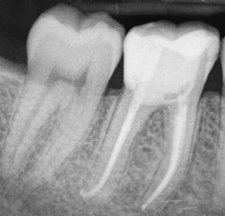

Wurzelkanalbehandlungen sind komplex. Es müssen auch feinste Wurzelkanäle gefunden, gereinigt und vollständig gefüllt werden. Im AD Zahnzentrum Dortmund werden daher Wurzelkanalbehandlungen von speziell ausgebildeten Zahnärzten (Endodontologen) durchgeführt. Modernste Technik unterstützt die Behandlung. Beispielsweise arbeiten die Experten unter einem hochauflösenden OP-Mikroskop oder vermessen die Wurzelkanäle elektronisch (Endometrie). Die hier zu sehenden Röntgenaufnahmen verdeutlichen, wie entscheidend kleinste Details für den Behandlungserfolg sein können.

Auf dem linken Bild ist eine unvollständige Wurzelfüllung erkennbar. Die dünne weiße Linie endet deutlich vor der Wurzelspitze. Die dunklen Schatten im Bereich der Wurzelspitzen weisen auf eine erneute Entzündung hin. Das rechte Bild zeigt denselben Zahn nach einer erneuten Behandlung (Revision). Alle Wurzelkanäle wurden vollständig gereinigt und bis zur Wurzelspitze dicht verschlossen – die Prognose für den Zahnerhalt ist dadurch sehr positiv.